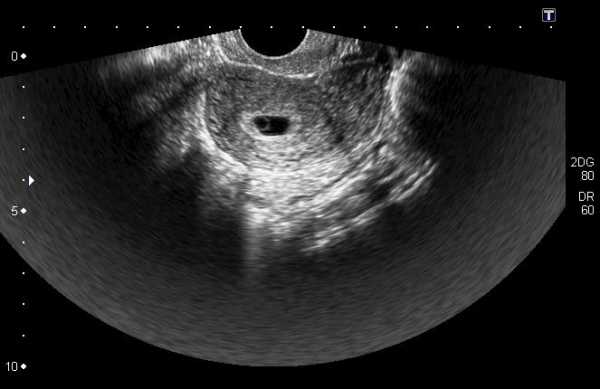

Плодное яйцо на УЗИ: размеры СВД по неделям

Сформированное плодное яйцо — это самый верный признак наступившей беременности. Оно имеет характерную форму овала и достаточно хорошо визуализируется на УЗИ на третьей неделе отсутствия менструации.

Плодное яйцо – это самый первый признак нормально протекающей беременности. Его можно разглядеть на УЗИ уже после 2 недель задержки менструации. Эмбрион же становится виден лишь на 5 неделе беременности. Но если на этом сроке врач диагностирует отсутствие эмбриона в плодном яйце – иными словами пустое плодное яйцо, то УЗИ спустя пару недель повторяют.

Плодное яйцо на первых неделях беременности имеет форму овала. И на УЗИ обычно оценивается внутренний его диаметр – СВД плодного яйца. Поскольку диаметр плодного яйца является вариабельной величиной, то существует погрешность в определении срока беременности по данному фетометрическому показателю.

В среднем такая погрешность составляет 1,5 недели. Срок беременности, как правило, определяют не только по этому показателю, но также используют значения КТР плода (копчико-теменной размер) и другие показатели.